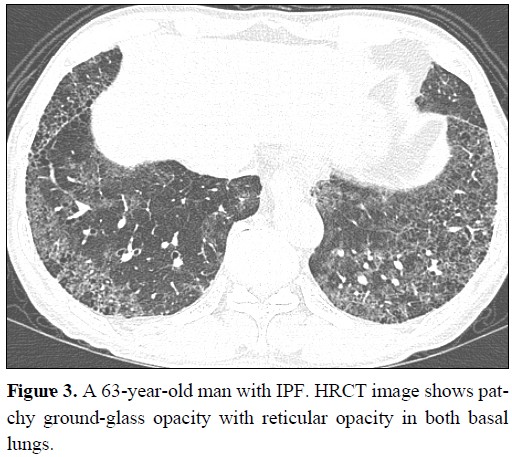

원인이 명확하지 않은 기질화 폐렴; 증상과 치료

기질화 폐렴은 섬유 모세포 혹은 근섬유 세포를 포함한 육아조직이 폐포(허파꽈리)와 세기관지 내에 증식하는 폐질환을 말합니다. 기질화 폐렴은 원인에 따라 특발성 기질화 폐렴과 이차성 기질화 폐렴으로 나눌 수 있습니다. 특발성 기질화 폐렴은 원인이 밝혀지지 않은 것이고, 이차성 기질화 폐렴은 다른 질환에 의해 발생한 기질화 폐렴입니다. 남녀가 모두 같은 비율로 발생하고, 평균 연령은 50~60세에서 흔하며, 흡연과는 무관하게 발병합니다. 1. 기질화 폐렴 원인 특발성 기질화 폐렴의 원인은 아직 밝혀지지 않았지만 면역체계의 이상이 관련되어 있을 것으로 추측됩니다. 이차성 기질화 폐렴의 원인으로는 다음과 같은 것들이 있습니다. - 자가면역질환 : 루푸스, 류마티스관절염, 쇼그렌증후군 등 - 감염성 질환 : 결핵..